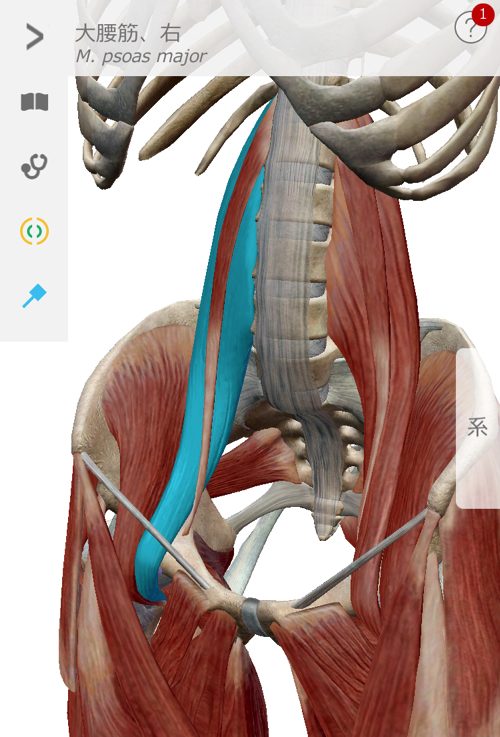

今回のぎっくり腰で特にしっかりと施術した場所はここ

大腰筋

これらの筋肉や腱の硬直を1つ1つ解いて

ズレやヨジレを丁寧に戻していく施術をさせて頂きました。